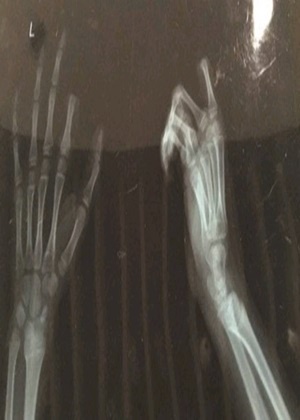

Um menino de 11 anos da cidade de Suzhou, na China, virou notícia nacional no país asiático após cortar o próprio dedo após uma briga com seu pai. Segundo a mídia local, o jovem, identificado apenas como Xiaopeng, teria reagido com raiva após muitas reclamações sobre seu uso excessivo do celular. O incidente aconteceu neste sábado. Tanto a mãe quanto o pai, que não foram identificados, dizem que estavam insatisfeitos com o menino, que não largava o celular desde que acordou naquele dia. Eles contam que achavam que era um mau-exemplo para o irmão mais novo, de 6 anos. A mãe teria se queixado ao pai, que então foi falar com o filho. O que era para ser uma conversa virou uma discussão, e, no que a imprensa chamou de "um ataque de raiva", agarrou uma faca na cozinha e cortou fora o dedo indicador esquerdo. Horrorizados, os pais levaram Xiaopeng e seu dedo para o Hospital da Universidade de Soochow. A operação de reimplante demorou três horas, mas, segundo a equipe cirúrgica, só se saberá se foi bem sucedida em uma semana, tempo mínimo para saber se o menino terá movimentos e sensação no dedo. "Crianças tem vasos sanguienos muito finos e frágeis, o que dificultou a operação. Se correr tudo bem, o impacto desse momento de loucura deve ser mínimo nos movimentos dele", disse o cirurgião chefe do hospital, Ren Zhourong, à mídia local.